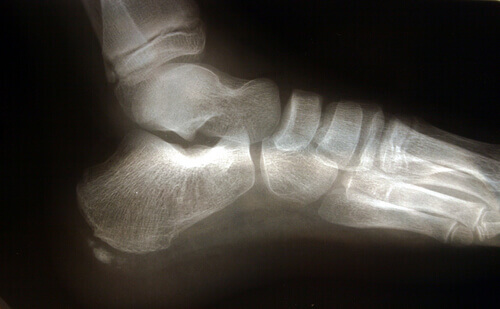

Jalan anatomiaa

On monia sellaisia anatomisia rakenteita, joilla on rooli alueen liiallisessa rasittamisessa.

Akillesjänne on nivelside, joka yhdistää gastrocnemius -lihakset (jotka tunnetaan arkikielessä pohkeina) ja soleusm -lihakset kantapääluuhun. Kutistuminen akillesjänteessä saa aikaan lisääntymisen kantapääluun kokemassa paineessa, ja samoin ilmenee lisääntymistä siinä paineessa, joka kohdistuu jalkapohjan jännekalvoon.

Toinen tekijä, joka kannattaa ottaa huomioon jalan rakennetta koskien, on se, millä tavalla jalka koskettaa maata. Tasaisella maalla jalkapohjalla on taipumus ylipronaatioon, ja jalkapohjan jännekalvo tulee tällöin venytetyksi enemmän, mikä lisää riskiä repeytymiselle, sillä kudokseen kohdistuu enemmän painetta.

Plantaarifaskiitti liittyy usein luun ulokkeeseen, vaikka tämä ei olekaan välttämätön syy.